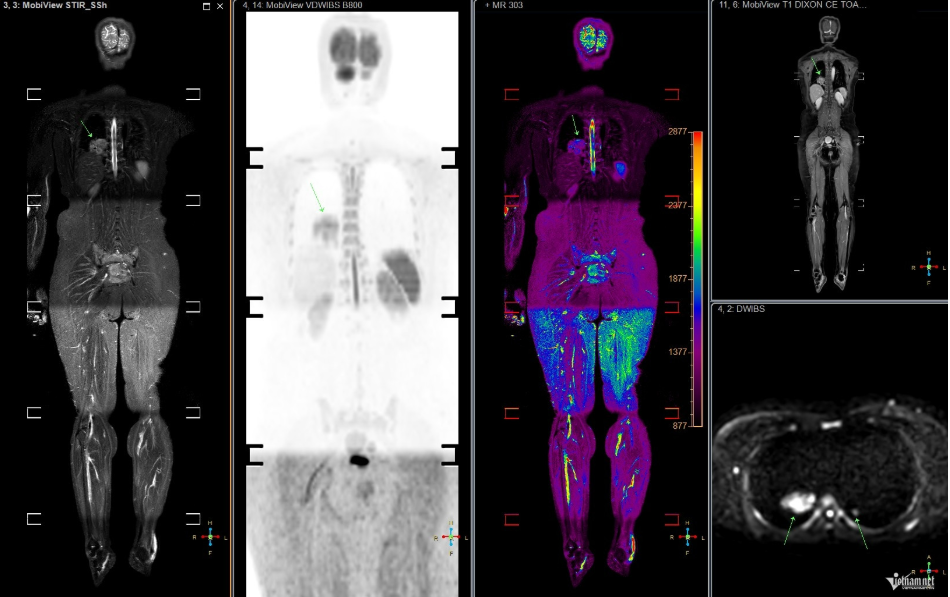

Tại bệnh viện, sau khi thực hiện các xét nghiệm và chụp chiếu, bác sĩ phát hiện chị T. có khối u ở phổi và các nốt mờ ở xương do di căn. Kết quả này khiến vợ chồng chị và bạn bè thân thiết bàng hoàng. Nhìn vào tấm phim MRI, từng nốt mờ ở phổi và xương được bác sĩ chỉ rõ, những lời giải thích như khắc sâu vào tâm trí chị.

Hình ảnh MRI toàn thân của bệnh nhân ung thư phổi. Ảnh: Minh Đức.

Về việc tầm soát sớm ung thư phổi, giáo sư Khoa cho biết những người có yếu tố nguy cơ như hút thuốc lá chủ động, thụ động có thể thực hiện qua chụp CT liều thấp, giúp phát hiện tổn thương nhỏ. Các kỹ thuật hiện đại như PET, PET/CT, PET/MRI, kết hợp với sinh học phân tử, hỗ trợ xác định đột biến gene, từ đó chọn phương pháp điều trị trúng đích.